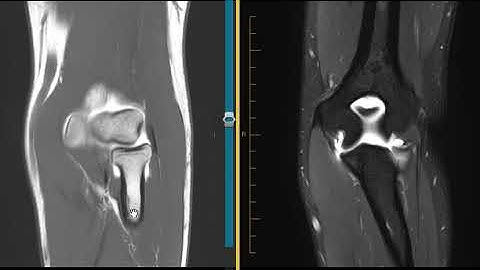

Transolecranon fracture dislocation- exposing coronoid and sublime tubercle #ortho #trauma